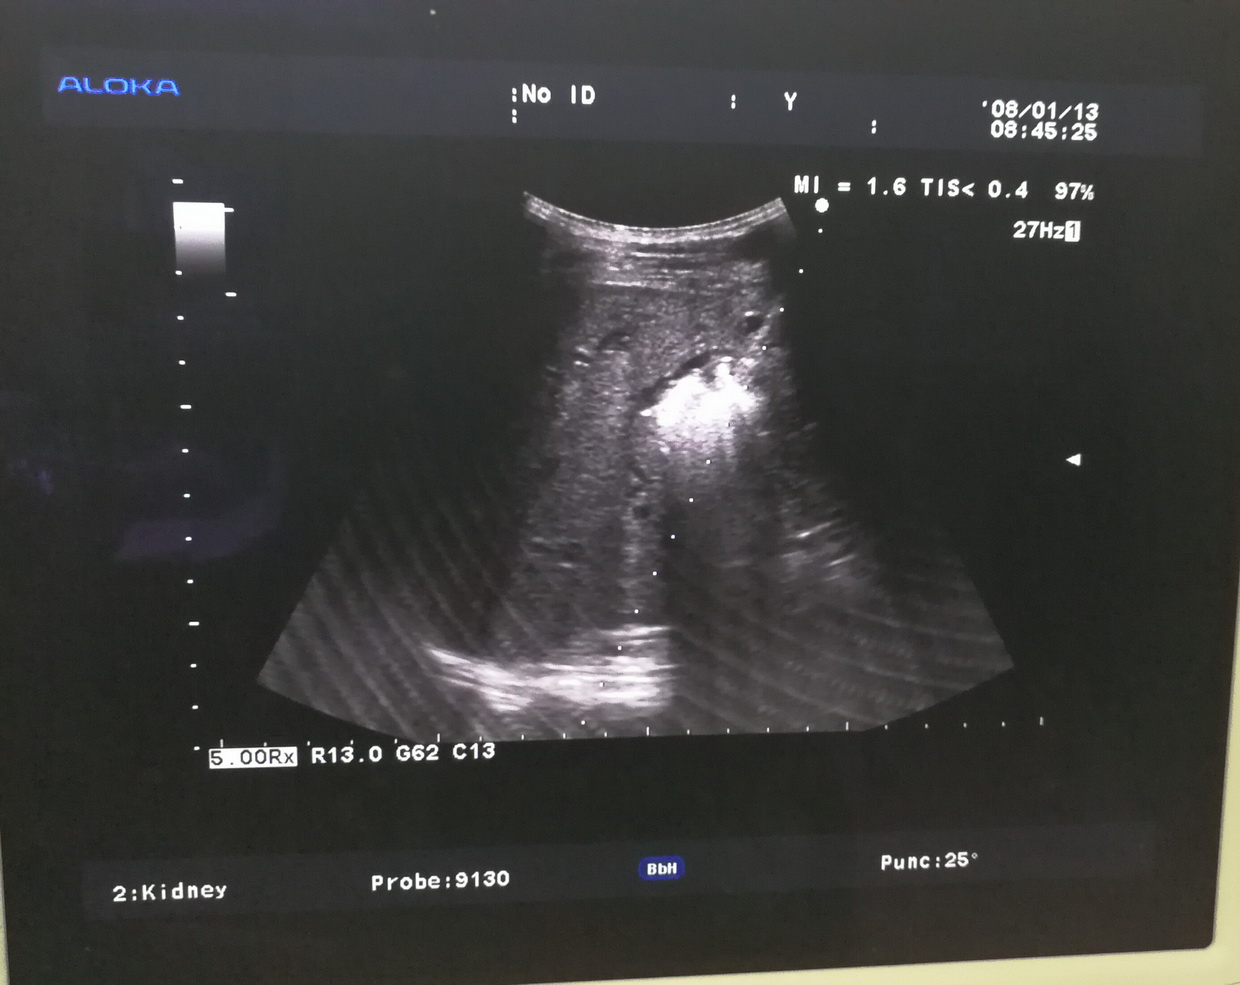

B型超声检查的范围很广,不同的检查部位,检查前的准备亦不相同。①腹部检查:包括肝、胆、胰、脾及腹腔等。一般应该空腹检查,因为进食后,胃及肠道产生气体,影响超声的穿透,空腹检查效果最好。②妇科检查:应该饮水憋尿,当膀胱充盈后,挤开肠管,让超声更好的穿透到盆腔,清晰的显示子宫及卵巢的正常与异常。③泌尿系检查:应该多饮水,当膀胱充盈后,内部的结石、肿瘤、息肉等,即能更好的显示。④体表肿物及病变:可以即时检查,一般无需特殊准备。⑤心脏及四肢血管检查,亦无需准备。

B型超声是超声的主要检查方法,虽然超声的发展突飞猛进,如内镜超声、超声造影、三维成像、弹性成像等等,都是在B型超声基础上发展起来的。因此,凡是进行超声工作的医师及被检查的患者,都应该了解B型超声的特点、检查前准备、检查范围及注意事项等等,以便更好地应用它来为被检查者服务服务。